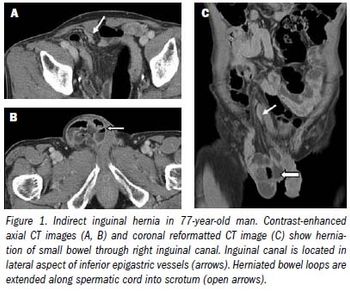

Although most hernias involving the anterior abdominal wall or groin can be diagnosed easily by inspection and palpation, imaging is the principal means of detecting internal, diaphragmatic, and other nonpalpable or unsuspected hernias.1,2